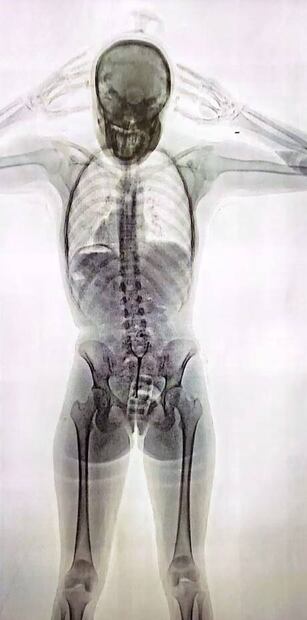

Poco después quedaría internada y detenida: las imágenes del escáner de rayos X revelaron la “presencia de cuerpos extraños en el organismo”. Ella misma confesó que llevaba “un paquete introducido por vía vaginal”. Eran 78 cápsulas con cocaína. La chica era, efectivamente, una “mula” de una banda narco.

“No solo respondió de forma dubitativa, también lo hizo de manera incongruente. Entonces, se decidió convocar a dos testigos y se le realizó un control corporal, no invasivo, mediante equipo de rayos x denominado Body Scan. El operador del equipo técnico visualizó una imagen dudosa en cuanto a la posible presencia de cuerpos extraños en el organismo”, explicó a LA NACION una fuente de la investigación.

Tras la “imagen dudosa” que arrojó el Body Scan, la PSA se comunicó con funcionarios del Juzgado en lo Penal Económico N° 6, a cargo del juez Aguinsky, que estaba de turno hasta el lunes pasado.

“El juez Aguinsky dispuso que se realice una requisa sobre la pasajera, detectándose que presentaba, en su zona genital interna [sic], elementos extraños, manifestando espontáneamente, que transportaba un paquete introducido vía vaginal”, sostuvo una fuente al tanto del expediente.

”En el hospital, los médicos confirmaron la presencia de cuerpos extraños introducidos vía vaginal y en el sistema digestivo de la pasajera”, agregaron los informantes consultados.